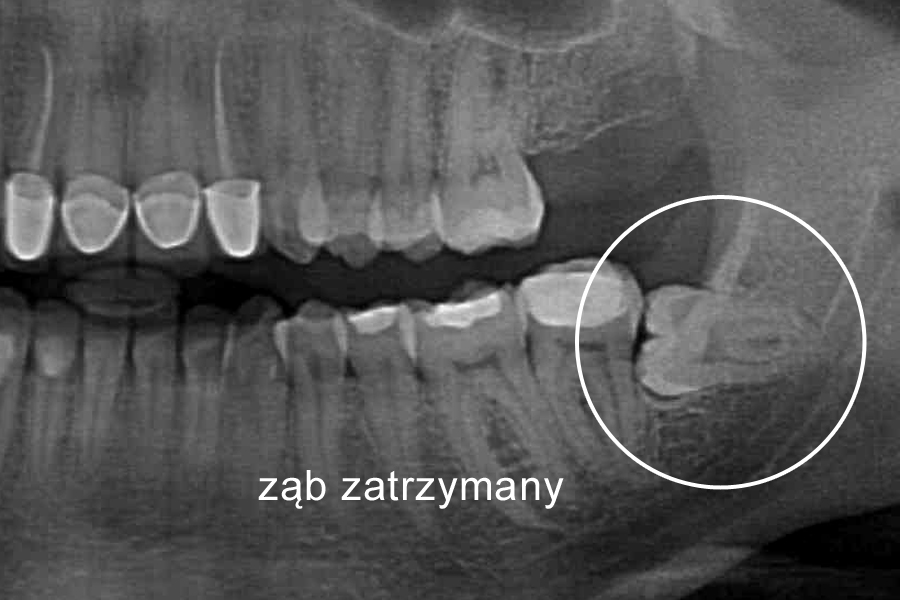

Ząb zatrzymany – warto wiedzieć

Ząb zatrzymany to w pełni wykształcony ząb stały, który po okresie fizjologicznego wyrzynania pozostaje w utkaniu kostnym szczęk lub żuchwy. Może być on zatrzymany całkowicie, gdy jest otoczony kością ze wszystkich stron lub zatrzymany częściowo, gdy ma koronę poza kością pokrytą jedynie dziąsłem.

Rozpoznanie zęba zatrzymanego opiera się na badaniu rentgenowskim.

Postępowanie lecznicze zależy od wieku chorego i warunków w jamie ustnej. Rozpatruje się możliwość ortodontycznego wprowadzenia zębów (zwłaszcza zębów siecznych i kłów) do łuku, ekstrakcję lub pozostawienie zatrzymanych zębów w kości.